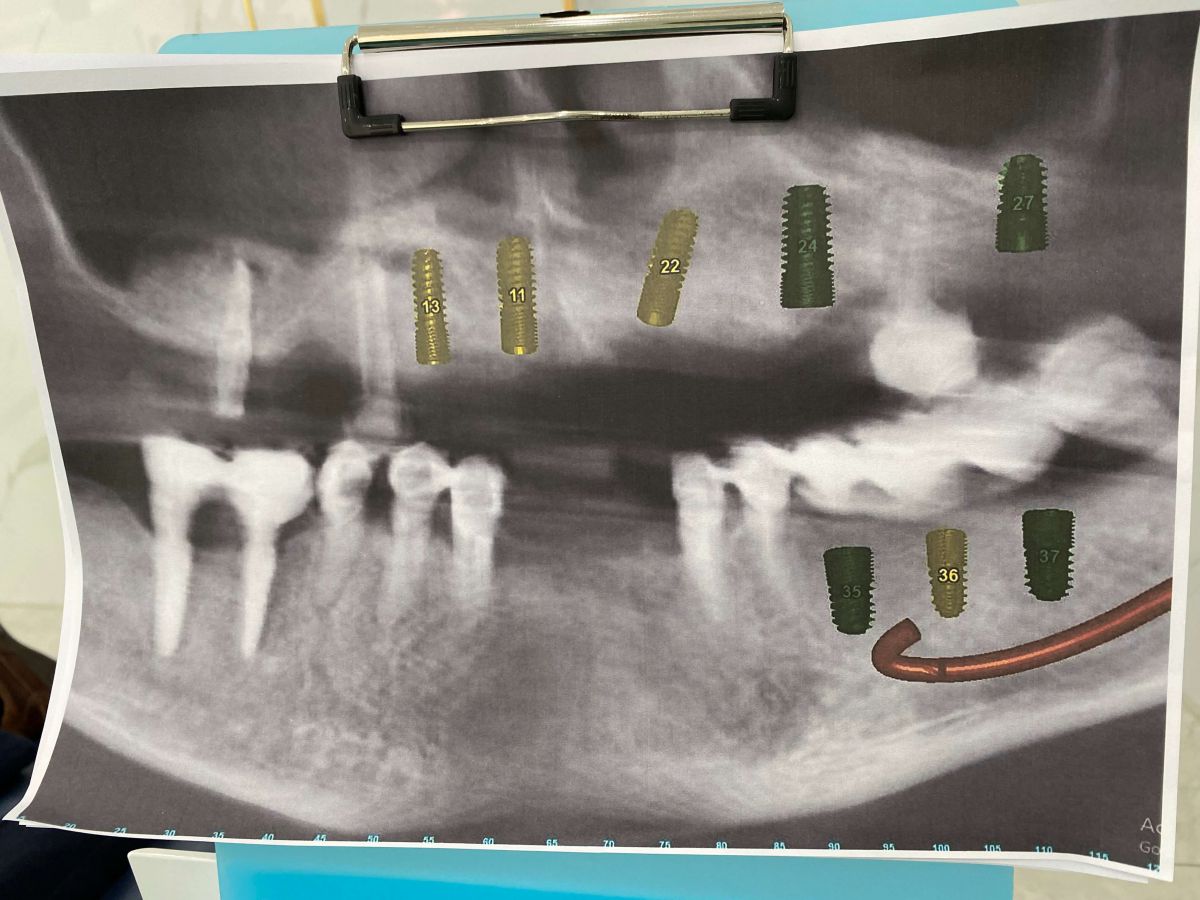

- Hàm trên: chỉ còn lại vài trụ Implant cũ đã được đặt cách đây hơn 10 năm, hiện nay có dấu hiệu tiêu xương quanh trụ, không còn đảm bảo chức năng nâng đỡ phục hình.

- Hàm dưới: nhiều mão sứ và cầu răng đã xuống cấp, lỏng, gãy, gây mất cân đối khớp cắn và ảnh hưởng đến khả năng ăn nhai.

- Xương hàm có dấu hiệu tiêu và mỏng, cần được đánh giá kỹ qua phim CT ConeBeam 3D để xác định có cần ghép xương, nâng xoang trước khi cắm trụ mới.

- Hàm trên: Cấy ghép Implant toàn hàm bằng kỹ thuật All-on-5 – giải pháp phục hồi tối ưu giúp tái tạo toàn bộ hàm răng trên chỉ với 5 trụ Implant, mang lại độ vững chắc và thẩm mỹ cao.

- Hàm dưới: Đặt thêm Implant Hiossen (Mỹ) để phục hình lại các răng mất, đảm bảo khả năng chịu lực tốt, tích hợp xương nhanh và tuổi thọ lâu dài.

Toàn bộ quy trình được thực hiện dưới sự hỗ trợ của công nghệ Hansafe độc quyền từ Hàn Quốc giúp cấy ghép chính xác, an toàn, giảm xâm lấn và rút ngắn thời gian hồi phục cho bệnh nhân.